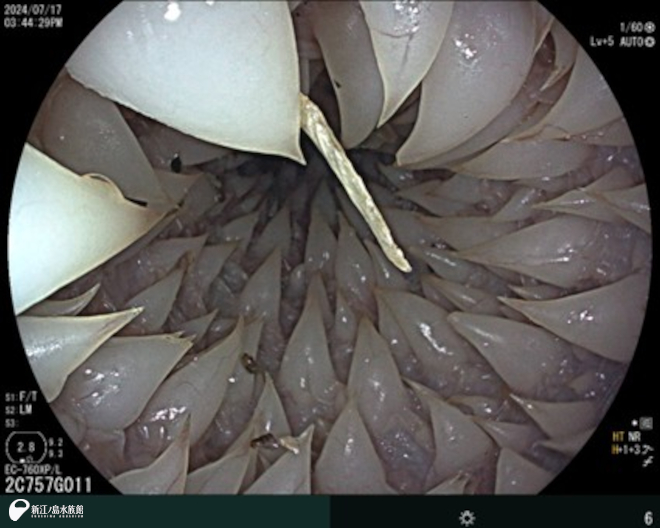

次は、内視鏡。

先端に超小型のカメラを搭載した細長い管を体内に挿入し、消化管や気管支など内部をリアルタイムの映像で観察、診断、治療することができます。胃潰瘍や異物誤飲の確認や除去、人工授精などで使用します。こちらも 2台の機械を持っていて、動物種や状態に合わせて使用しています。

2024年 アオウミガメ「ティダ」の食道のようすです。ウミガメ類は口から食道にかけて、後ろ向きにとげとげした突起がたくさん並んでいます。捕獲した獲物の逆流を防ぐ役割を果たしているといわれています。ウミガメの食道はとげとげしていると聞いたことはありましたが、初めて自分の目で見た時は本当にとげとげしているんだ!と思ったことを今でも鮮明に覚えています。